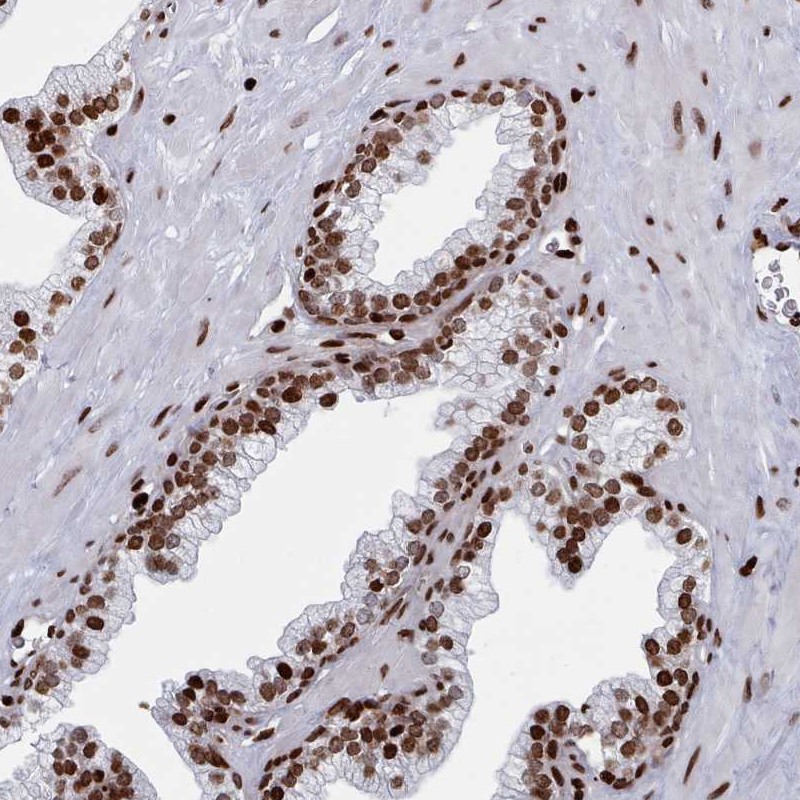

Immunohistochemical staining of human prostate shows strong nuclear positivity in glandular cells.